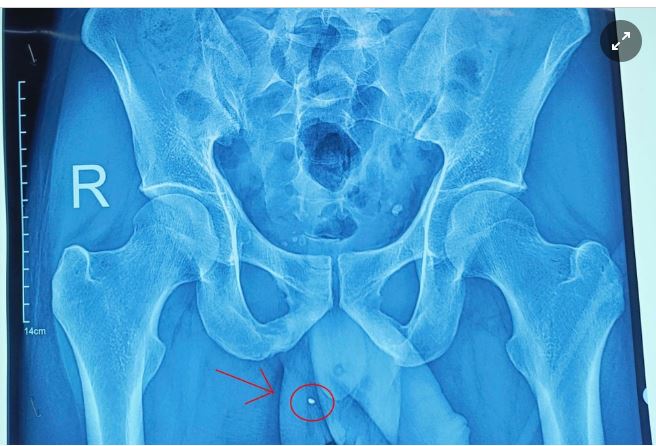

Ảnh chụp mảnh kim loại nằm trong vùng bìu người bệnh. Ảnh: BVCC.

Người đàn ông 33 tuổi, ở huyện Chiêm Hoá, tỉnh Tuyên Quang, đến khám tại Bệnh viện Đa khoa tỉnh Tuyên Quang trong tình trạng sưng nề, chảy máu vùng dương vật và bìu bên phải.

Bệnh nhân kể lại trong quá trình làm việc, anh sử dụng súng bắn đinh. Bất ngờ, mảnh kim loại từ súng văng ra và đâm xuyên vào cơ quan sinh dục.

Ngay khi nhập viện, người bệnh được làm các xét nghiệm và lập tức chuyển lên phòng mổ cấp cứu. Trong quá trình phẫu thuật, ê-kíp phát hiện bệnh nhân có vết thương "xuyên táo" tinh hoàn phải (từ đuôi mào tinh hoàn đến đầu mào tinh hoàn), đang rỉ máu.

Các bác sĩ đã phẫu thuật lấy ra dị vật kim khí (kích thước khoảng 4 mm), sau đó cầm máu kỹ, bảo tồn tinh hoàn và đặt 1 dẫn lưu cho bệnh nhân.